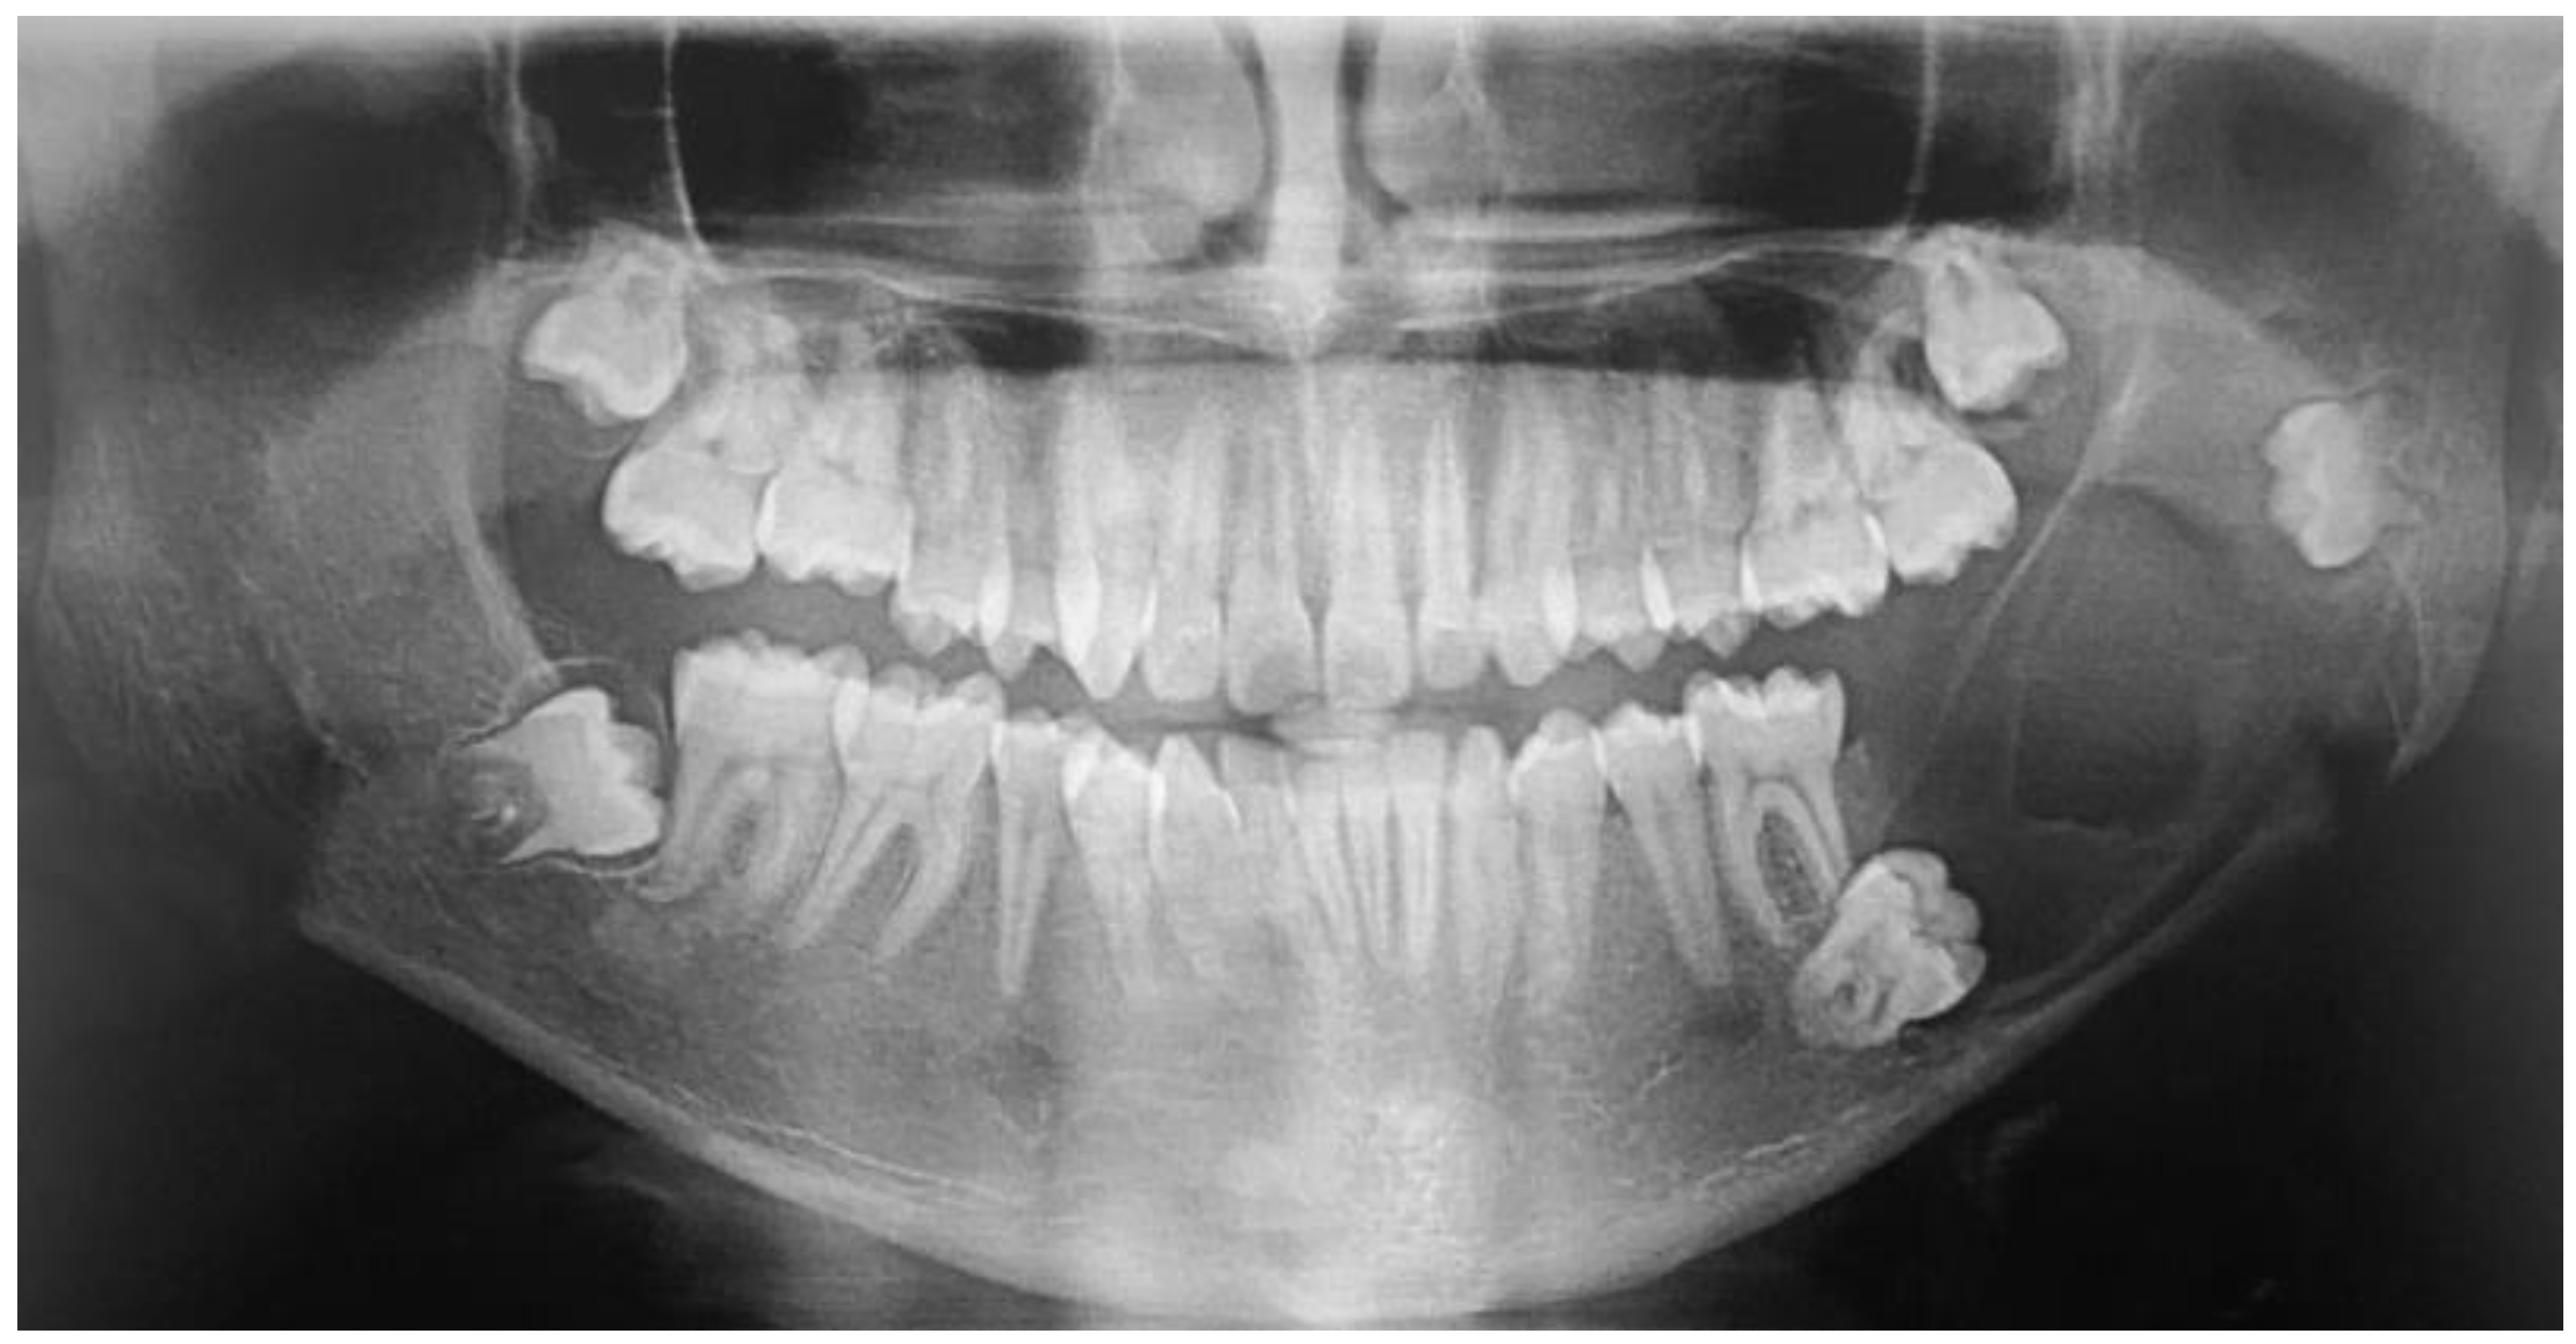

2.1. Case 1

2.2. Case 2